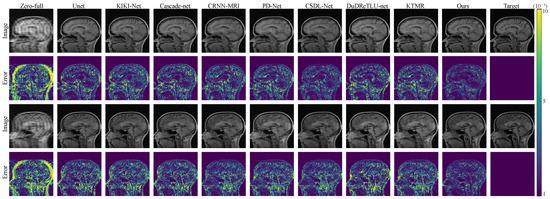

As shown in Figure 4 and Figure 5, both in the error maps and the reconstructed images, our algorithm demonstrates smaller errors and more accurate texture structures, which is similar to the results observed in the FastMRI dataset.

Figure 4. The reconstruction results and error maps are compared among 8 algorithms under 4× acceleration on the Calgary-Campinas dataset.

Electronics 12 04742 g004